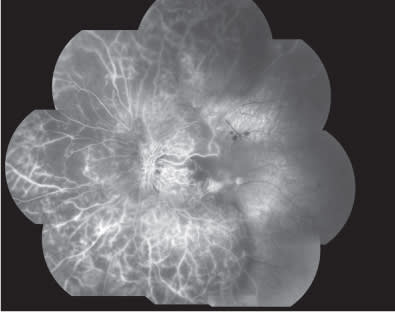

The patient was evaluated one month later, and he complained of a severe visual acuity impairment in the LE, which had occurred a few days before. BCVA was 0.8 in the RE and 0.05 in the LE. Biomicroscopic examination revealed a hyperemic and swollen optic disc, with several retinal hemorrhages. Retina at the posterior pole was pale, with attenuation and sheathing of arterial vessels. FA showed a delayed optic disc and arterial filling with extensive retinal ischemia involving both posterior pole and periphery (Figures 4 and 5). The picture was consistent with the diagnosis of anterior ischemic optic neuropathy associated with retinal arterial occlusion. Carotid doppler ultrasound, electrocardiogram and echocardiogram examinations revealed no alterations.

Figure 5. Composite fluorescein angiography in the early phases showing a delayed optic disc and arterial filling with extensive retinal ischemia involving both posterior pole and periphery.